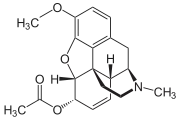

- Esters of morphine opiates: slightly chemically altered but more natural than the semi-synthetics, as most are morphine prodrugs, diacetylmorphine (morphine diacetate; heroin), nicomorphine (morphine dinicotinate), dipropanoylmorphine (morphine dipropionate), desomorphine, acetylpropionylmorphine, dibenzoylmorphine, diacetyldihydromorphine;[261][262]

Several semi-synthetic opioids were developed in Germany in the 1910s. The first, oxymorphone, was synthesized from thebaine, an opioid alkaloid in opium poppies, in 1914.[228] Next, Martin Freund and Edmund Speyer developed oxycodone, also from thebaine, at the University of Frankfurt in 1916.[229] In 1920, hydrocodone was prepared by Carl Mannich and Helene Löwenheim, deriving it from codeine. In 1924, hydromorphone was synthesized by adding hydrogen to morphine. Etorphine was synthesized in 1960, from the oripavine in opium poppy straw. Buprenorphine was discovered in 1972.[228]